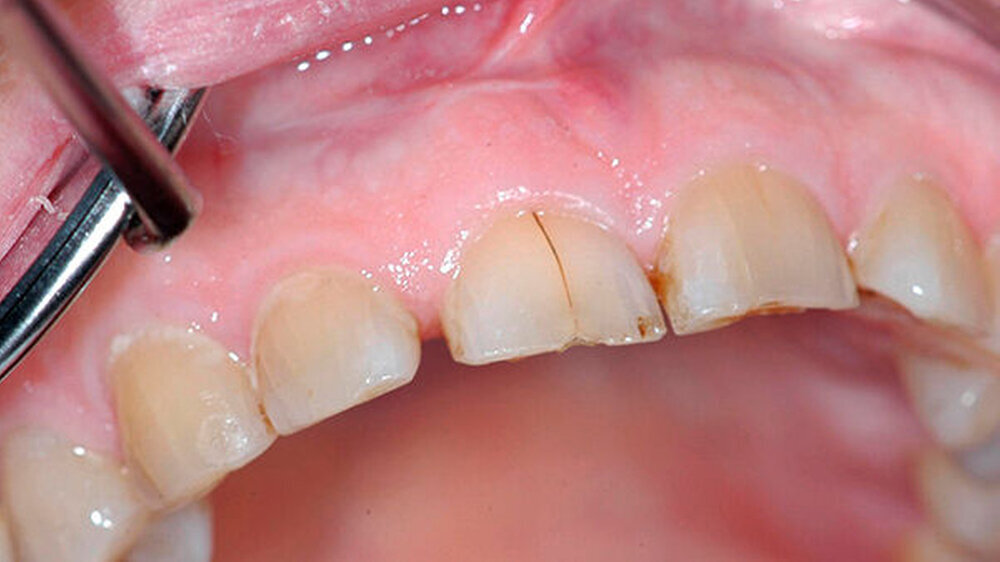

Bei der Vorstellung in der Poliklinik zeigte sich klinisch eine Schmelzfraktur auf der bukkalen Fläche des Zahns 11 (Abbildung 1). Die Messung der Taschensondierungstiefe (TST) ergab an dieser Stelle lokal begrenzt einen Wert von 7 mm (Abbildung 2). An allen übrigen Messpunkten lag eine physiologische TST von 3 mm vor.